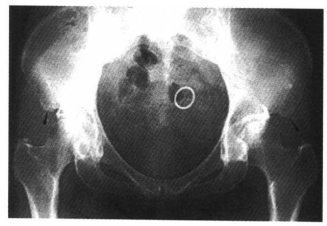

11.坐骨、耻骨软骨联合处不规则愈合,为正常变异,一般为双侧对称,有时仅为一侧,不要误认为骨缺血坏死(图11)。

图11 坐、耻骨联合处不规则愈合,不要误认为坐、耻骨联合处缺血坏死